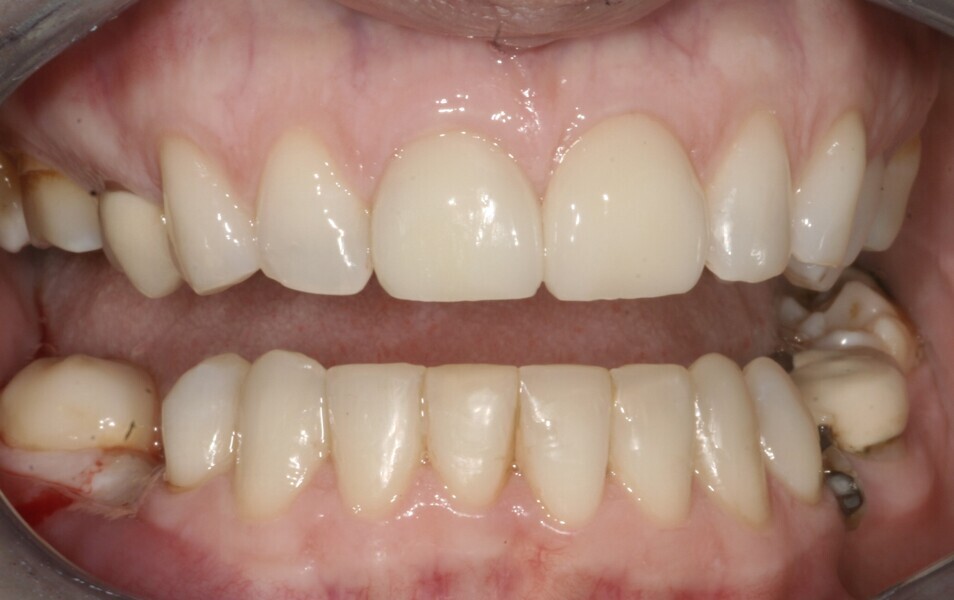

The occlusion was reviewed and readjusted about one month later to ensure that any maximum intercuspation and centric relation slide had been accounted for. The anterior contacts were readjusted and balanced at this point. The two maxillary central restorations were replaced with a new ceramic crown and a veneer (Figs. 7 & 8).

The patient’s occlusion settled over a two- to threemonth period. The result was not perfect, but we were working within a limited budget. After about six years, the bridges in the mandibular arch were replaced at the patient’s own pace.

In 2021, the patient decided to have the two maxillary central incisor restorations replaced with a lithium disilicate crown and veneer (Fig. 13). The maxillary palatal platforms created with Venus Diamond in 2017 were still functional, and the repaired mandibular central incisal edge was still intact (Figs. 14 & 15). The original edge bonding on the other mandibular teeth still remained in place, 17 years later.

Fig. 13: 2021—the two maxillary central incisor restorations replaced with a lithium disilicate crown and veneer.

Fig. 14: 2021—the repaired mandibular central incisal edge still intact.

Fig. 15: 2021—the maxillary palatal platforms created with Venus Diamond still functional.